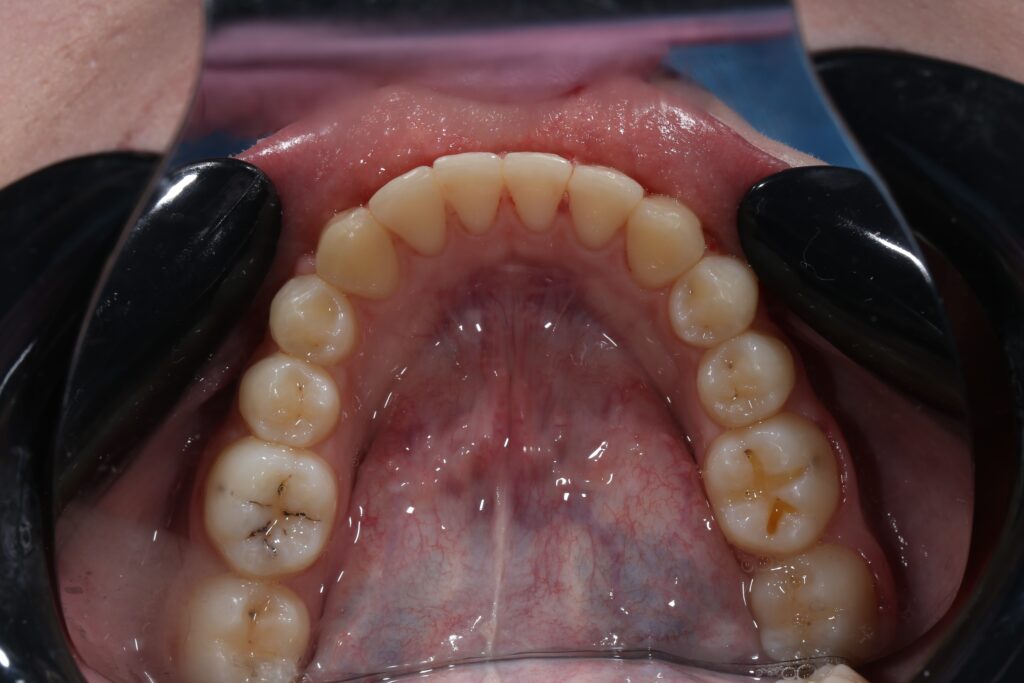

Ситуация до лечения

Диагноз: дистальный прикус, сужение, удлинение верхнего зубного ряда, скученность фронтальной группы зубов на нижней челюсти. Лечение проводилось самолигирующей брекет-системой Damon Q, срок лечения составил 2 года и 2 месяца.

Ситуация до лечения брекетами